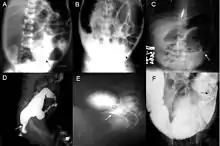

Definitive diagnosis is made by suction biopsy of the distally narrowed segment.[26] A histologic examination of the tissue would show a lack of ganglionic nerve cells. Diagnostic techniques involve anorectal manometry,[27] barium enema, and rectal biopsy. The suction rectal biopsy is considered the current international gold standard in the diagnosis of Hirschsprung's disease.[28]

Radiologic findings may also assist with diagnosis.[29] Cineanography (fluoroscopy of contrast medium passing anorectal region) assists in determining the level of the affected intestines.[30]